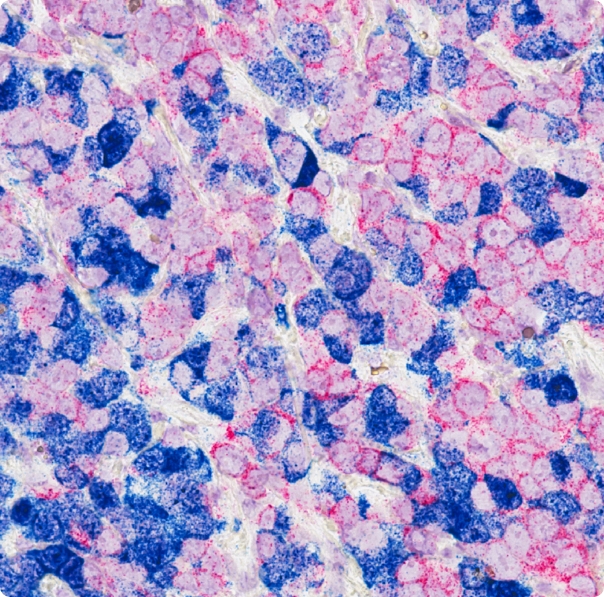

Gotovo trećinu svih malignih tumora kod žena čini rak dojke koji je visoko zastupljen i među uzrocima smrti kod žena. U cijelom svijetu ulažu se veliki napori kako u ranom otkrivanju bolesti, tako i u njenom liječenju. Najteži oblik tumora su metastatski. Metastaza znači da se rak proširio sa mjesta gdje je započeo u druga tkiva daleko od originalne lokacije tumora. Od ukupnog broja žena dijagnosticiranih karcinomom dojke, kod jedne od tri žene se razvio metastatski stadij bolesti. Najčešće metastaze raka dojke su jetra, pluća, kosti, mozak te limfni čvorovi. Trenutak kada žena dobije dijagnozu metastatskog raka dojke jedan je od najbolnijih u njenom životu. Ipak, zahvaljući novim savremenim terapijama ove žene danas mogu dugo i kvalitetno živjeti.

Metastatski rak dojke nije moguće izliječiti, ali pacijentice danas mogu dugo živjeti, uz održavanje dobre kvalitete života, zahvaljujući novim i modernim terapijama. Osim lokalnog liječenja, poput hirurškog zahvata i zračenja, postoji i sistemsko liječenje koje podrazumijeva primjenu lijekova. Ono uključuje kemoterapiju, antihormonsku terapiju, uvriježenu kao hormonsku ili endokrinu, a odnedavno i kombinaciju antihormonske terapije i nove skupine lijekova koji se nazivaju CDK4/6 inhibitori, a koji djeluju ciljano na malignu stanicu. Ciljana kombinirana terapija predstavlja savremenu terapijsku opciju koja produljuje vrijeme bez napredovanja bolesti. Time se odgađa primjena kemoterapije, a bolesnicama osigurava bolja kvaliteta života, bez nuspojava kakve nosi kemoterapija koja sistemski djeluje na organizam, izazivajući mučnine, opadanje kose i slično. Kod uznapredovalog raka dojke primarno je odgoditi vrijeme do progresije bolesti, zatim maksimalna kontrola simptoma te produženje kvalitetnog života pacijentica.